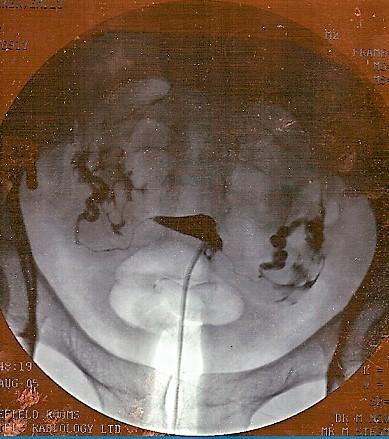

In the image below, the small black triangle shape in the middle is a normal womb filled with dye. The dye comes in through the tube which is at the base of the triangle and goes out to the edge of the photo. There are two very thin lines of dye coming away from the points of the triangle and these are normal Fallopian tubes, filled with dye. The larger areas of dye at either side is where the dye has spilled out of the normal tubes.

Hysterosalpingogram

By jemsweb [CC BY-SA 2.0 (https://creativecommons.org/licenses/by-sa/2.0)], via Wikimedia Commons